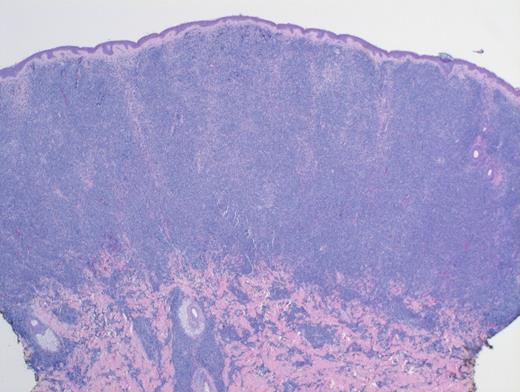

Low-Power H&E. Extensive, monotonous infiltrate composed of small- to medium-sized cells extending into the dermis. The epidermis is not involved (magnification x400).

TBPDCN is a rare, clinically aggressive neoplasm seen typically in adults. It has been rarely reported in the pediatric population. The disease tends to involve multiple sites, but skin is a common location. BPDCN is characterized by a monotonous infiltrate composed of undifferentiated medium-sized blastic cells with dispersed chromatin. The infiltrate spares epidermis and adnexal structures but extends deeply into the subcutaneous tissue. The typical immunophenotypic profile is CD4+, CD56+, and CD123+ neoplasm. However, a subset of cases (8%) are CD56-negative. An extensive panel of immunohistochemical stains (including TCL1A, CD303, and more recently, TCF4) further help to diagnose. Whenever possible, both flow cytometry and cytogenetics should be performed.